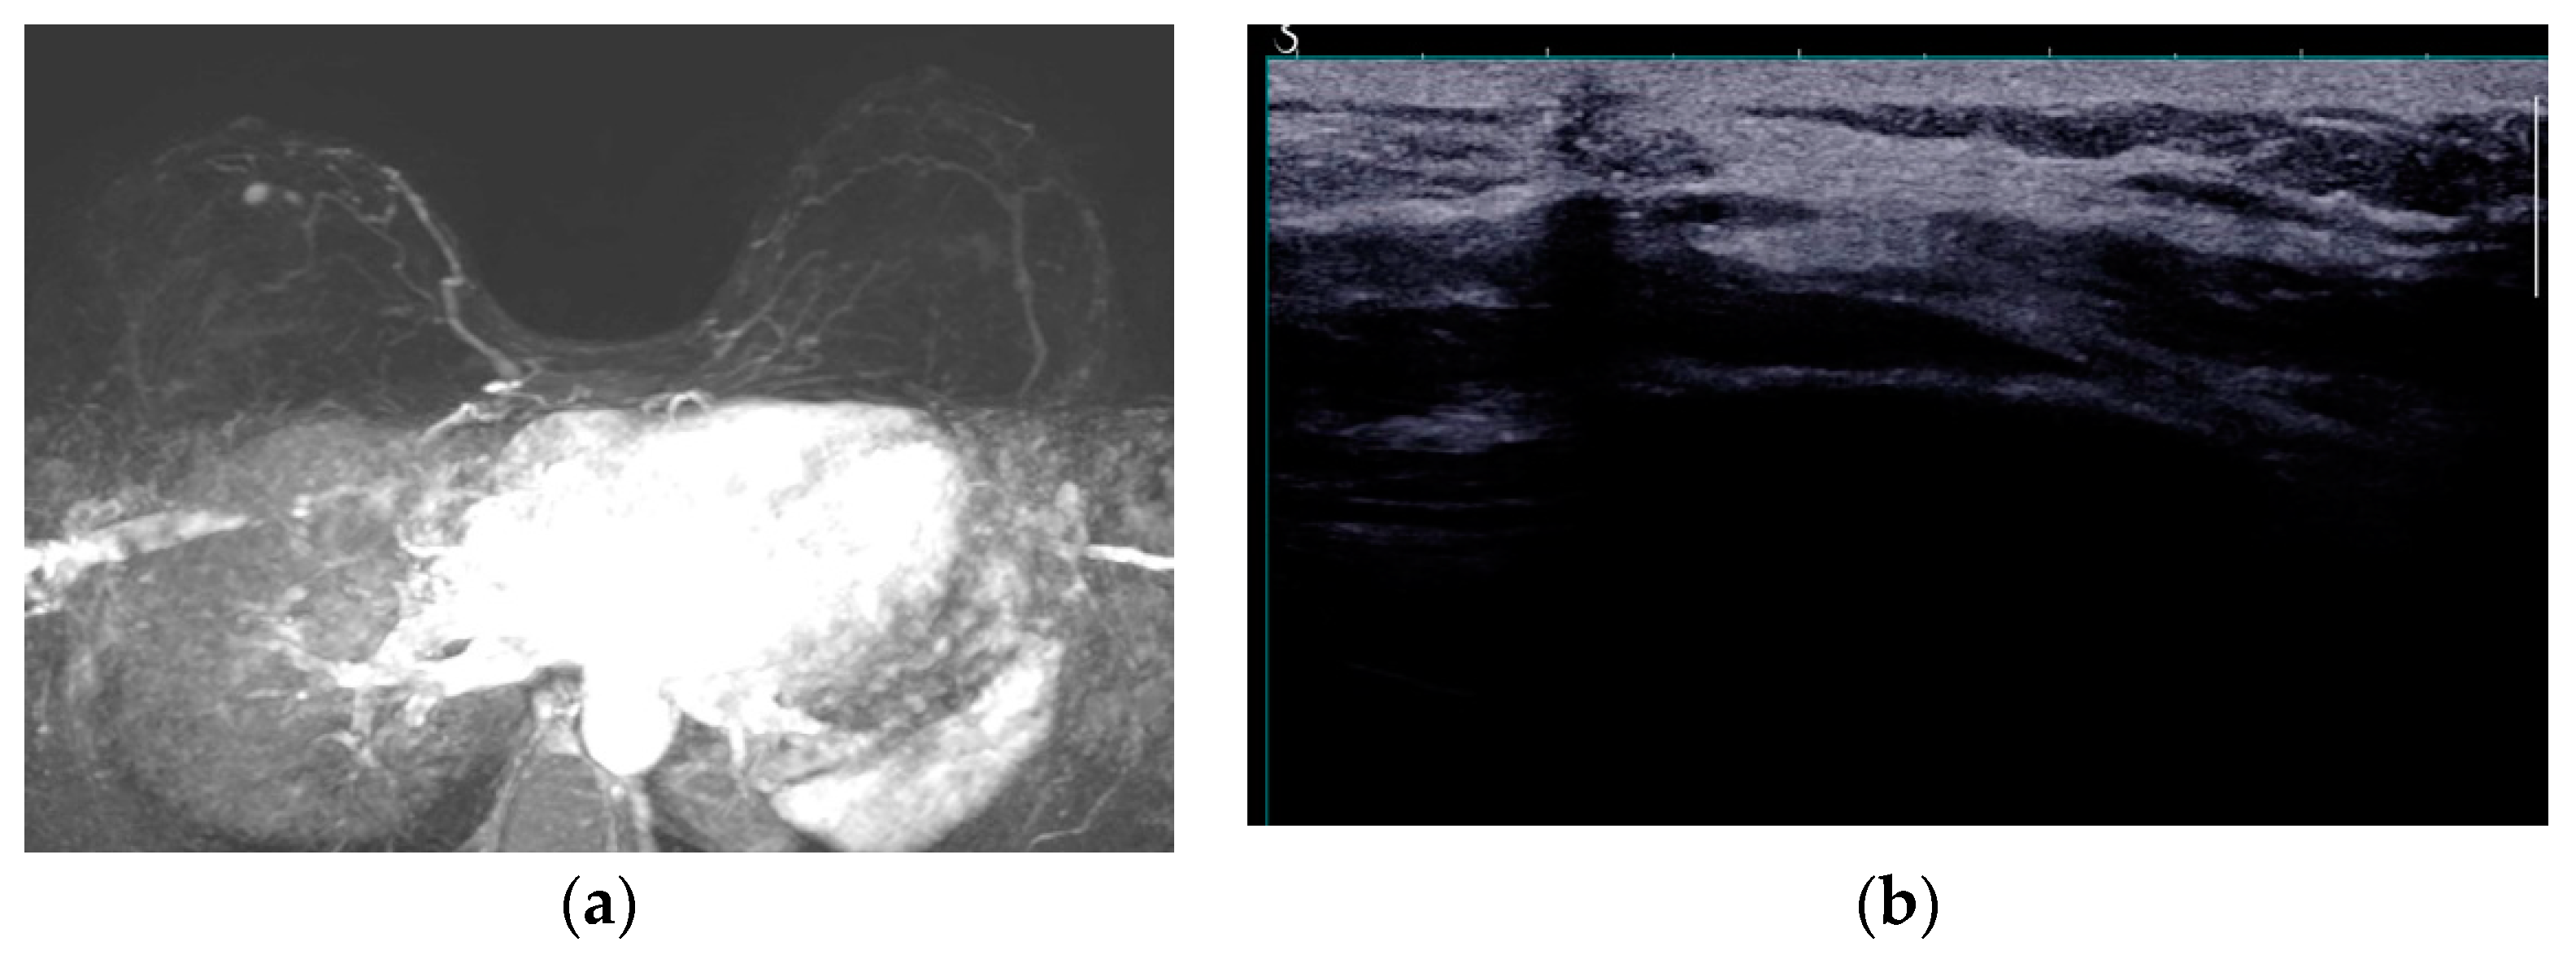

The typical mammographic appearance of an implant is a radiopaque oval mass with smooth margins whose density varies depending on the filling material (Figure 3a). A band of soft density tissue surrounding the implant, with or without calcifications represents the thick fibrous capsule that is formulated after the implant insertion as a result of a foreign body reaction. Folds within the implant and the valve may be visible with the appropriate mammographic technique [47].

Ultrasonographically both saline and silicone implants are anechoic and the shell appears either as one echogenic line or as parallel echogenic lines. Internal folds may be recognized as wavy lines without disruption. The fibrous capsule is visible as an echogenic line parallel to the implant’s shell, sometimes with calcifications producing focal acoustic shadowing (Figure 3b). A small peri-implant fluid effusion is a normal finding. At implants with expanders the valve is visible and caution should be taken so that partially expanded implants should not be mistaken for ruptured implants [47].

Figure 3. Mediolateral oblique MLO mammography view and ultrasound (US) of the right breast after mastectomy and reconstruction with a single lumen silicone implant (a) At the MLO view the implant appears as a homogenous radiopaque oval mass with smooth borders; (b) On US the implant is anechoic. The intact shell appears as echogenic line (yellow arrows) and the fibrous capsule is seen as a parallel echogenic line (red arrows).